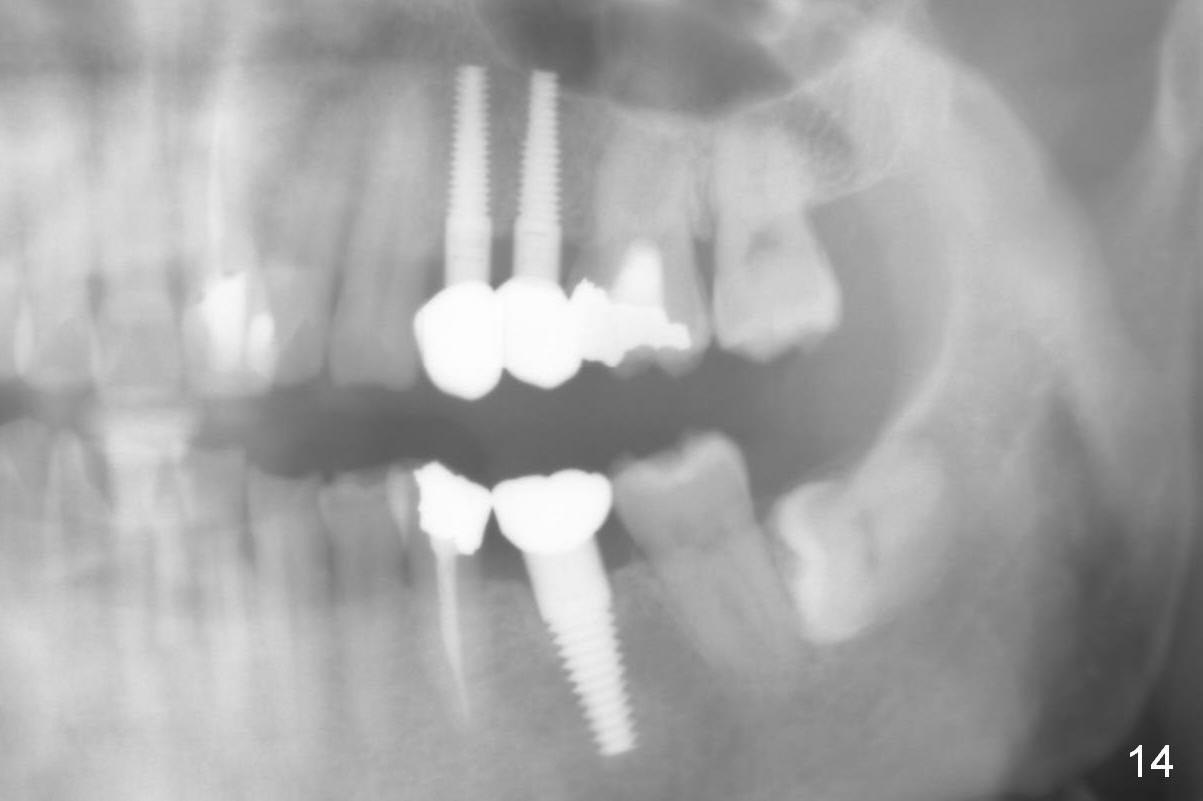

There is no relapse of intrusion for 2 years (Fig.14; 2 years post cementation for #12,13,30).